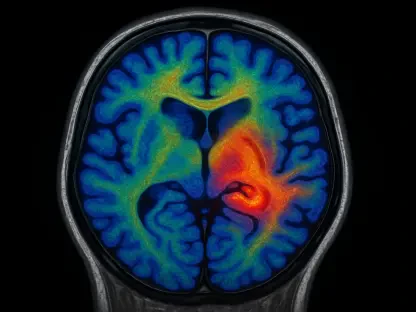

Can AI Revolutionize Brain Abnormality Detection in MRIs?

Picture a hospital radiology department swamped with thousands of MRI scans, each holding the key to a patient’s life-changing diagnosis, yet delays stretch on for weeks due to a shortage of experts. What if a machine could step in, instantly flagging critical brain abnormalities like strokes or